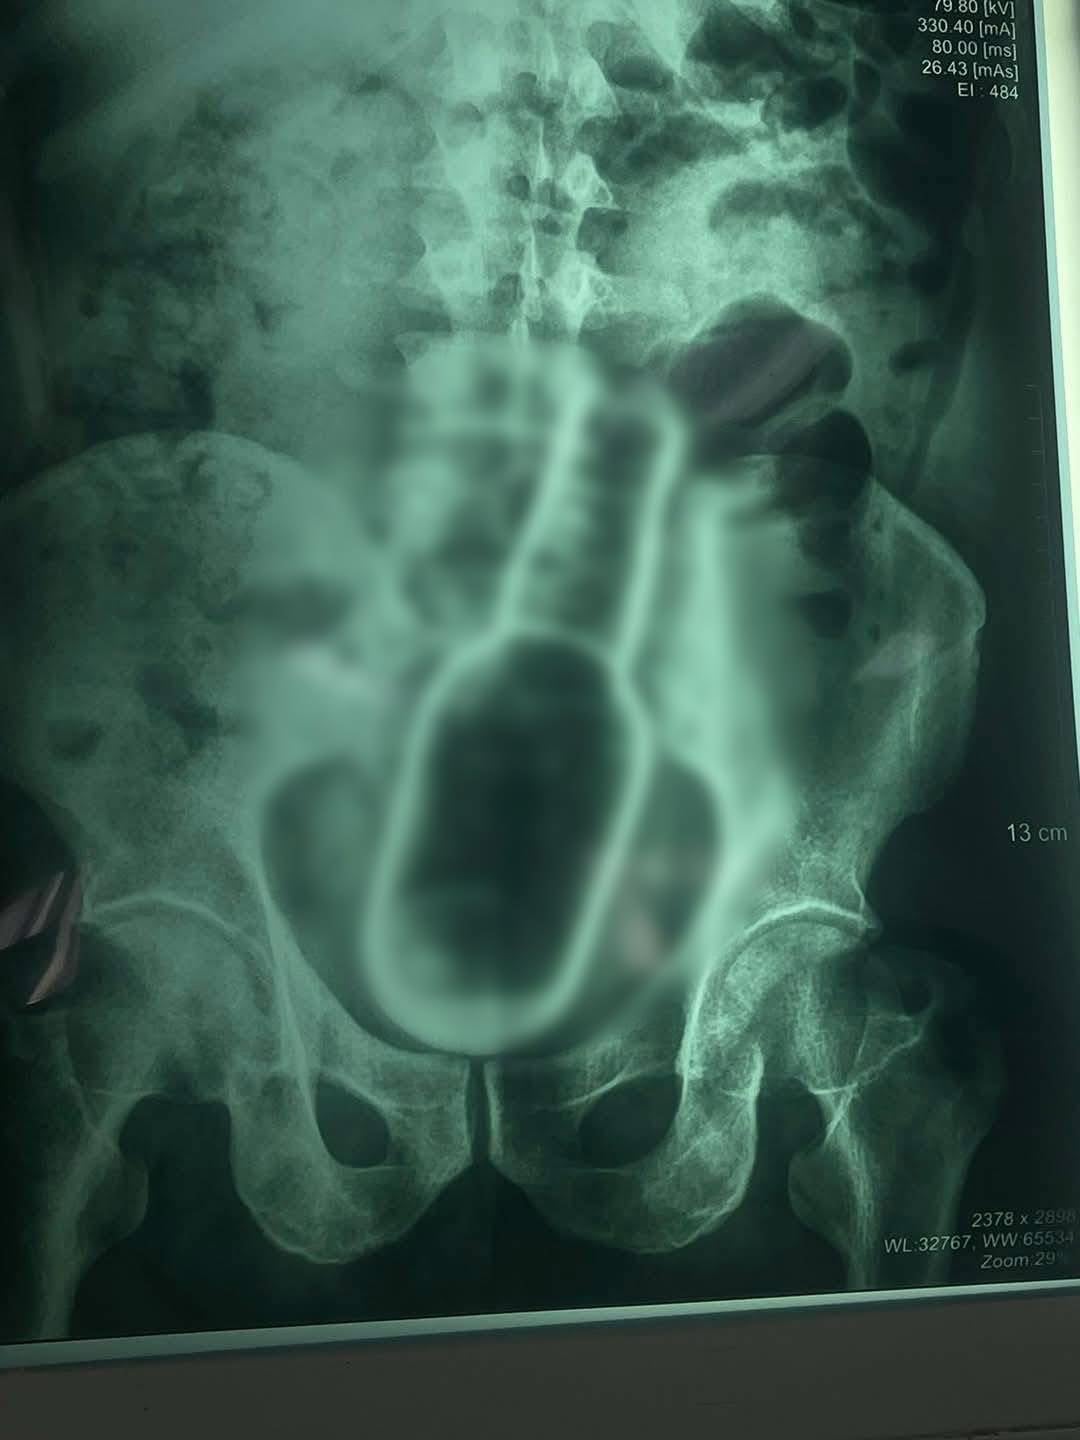

Una vez en el hospital, fue atendido por el equipo de urgencias, quienes, tras realizarle varios estudios, entre ellos radiografías, confirmaron la presencia del objeto extraño.

Debido a la posición y tamaño del recipiente, los médicos determinaron que era necesario intervenir quirúrgicamente al paciente. La operación se realizó alrededor de las 10:00 de la mañana y, según el informe preliminar, se logró extraer el objeto sin mayores complicaciones. El paciente se encuentra estable y bajo observación médica.